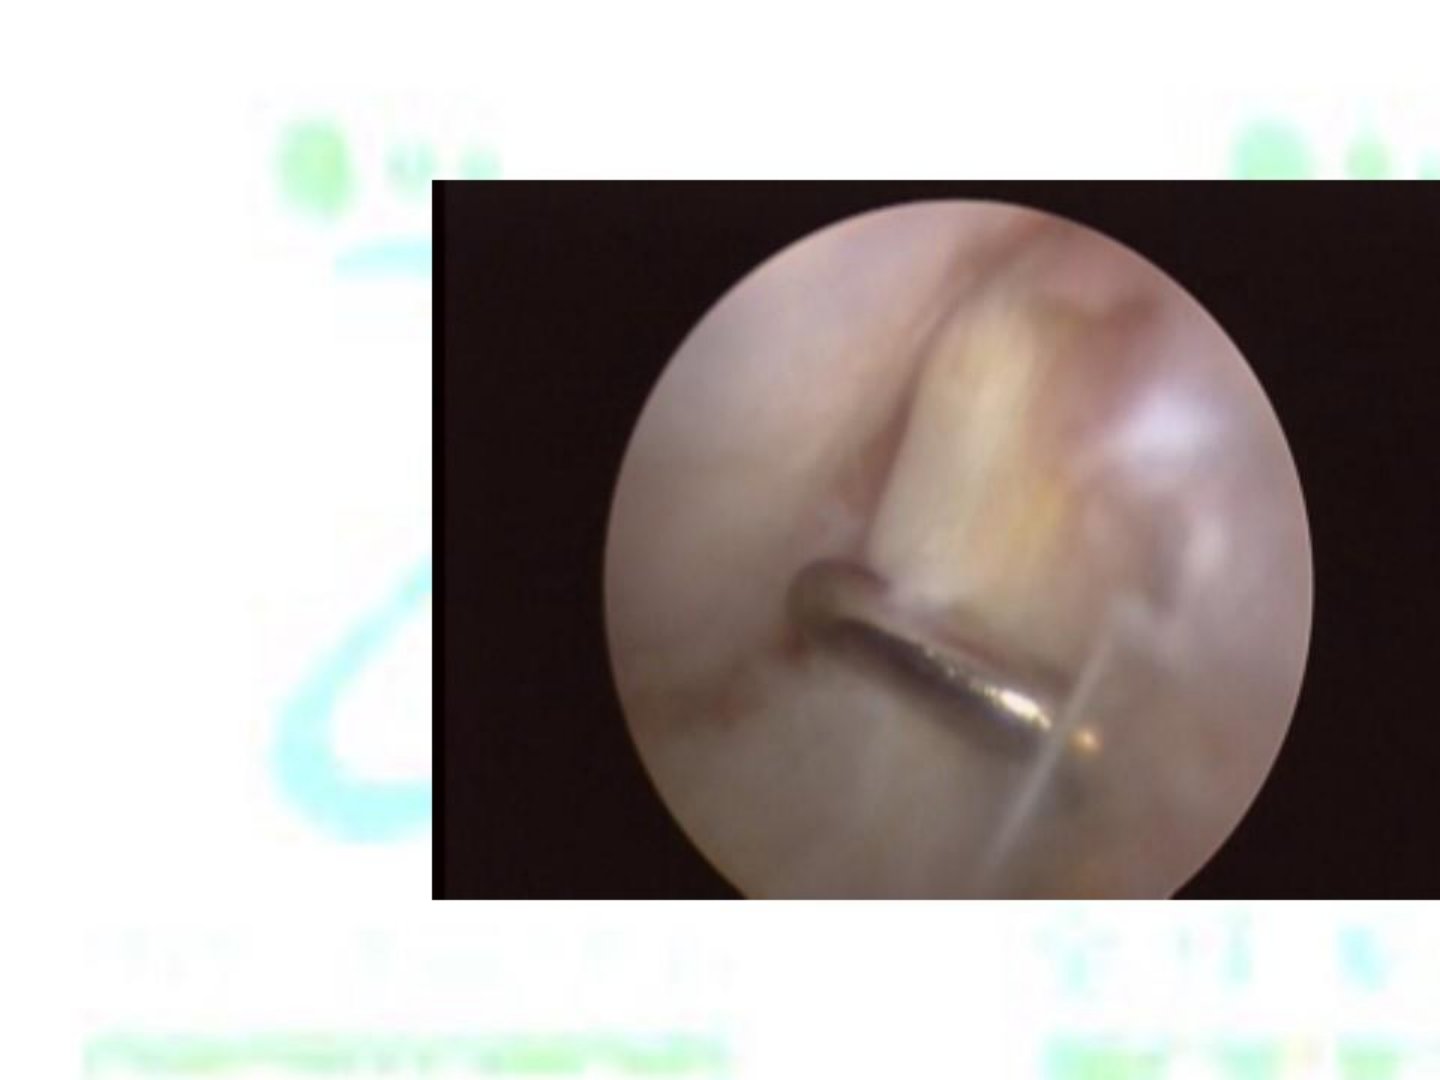

全关节镜下踝关节外侧韧带重建摘要全关节镜下踝关节外侧韧带重建是针对踝关节外侧韧带损伤的有效治疗手段。手术适应证主要为踝关节外侧韧带反复损伤致慢性不稳保守治疗无效者。手术过程中借助关节镜的清晰视野医生能精准定位损伤部位减少对周围正常组织的损伤。通常取自体肌腱(如腓骨长肌腱)作为移植物通过特殊器械和技巧在关节镜下将移植物准确固定于距骨和腓骨的相应解剖位置重建踝关节外侧韧带的稳定性。该术式优势明显切口小术后疼痛轻、疤痕小患者恢复快能尽早开展康复训练降低关节粘连等并发症发生风险。不过手术对医生技术要求较高需具备丰富的关节镜操作经验。术后需遵循医嘱进行规范的康复训练以促进踝关节功能恢复提高患者生活质量。